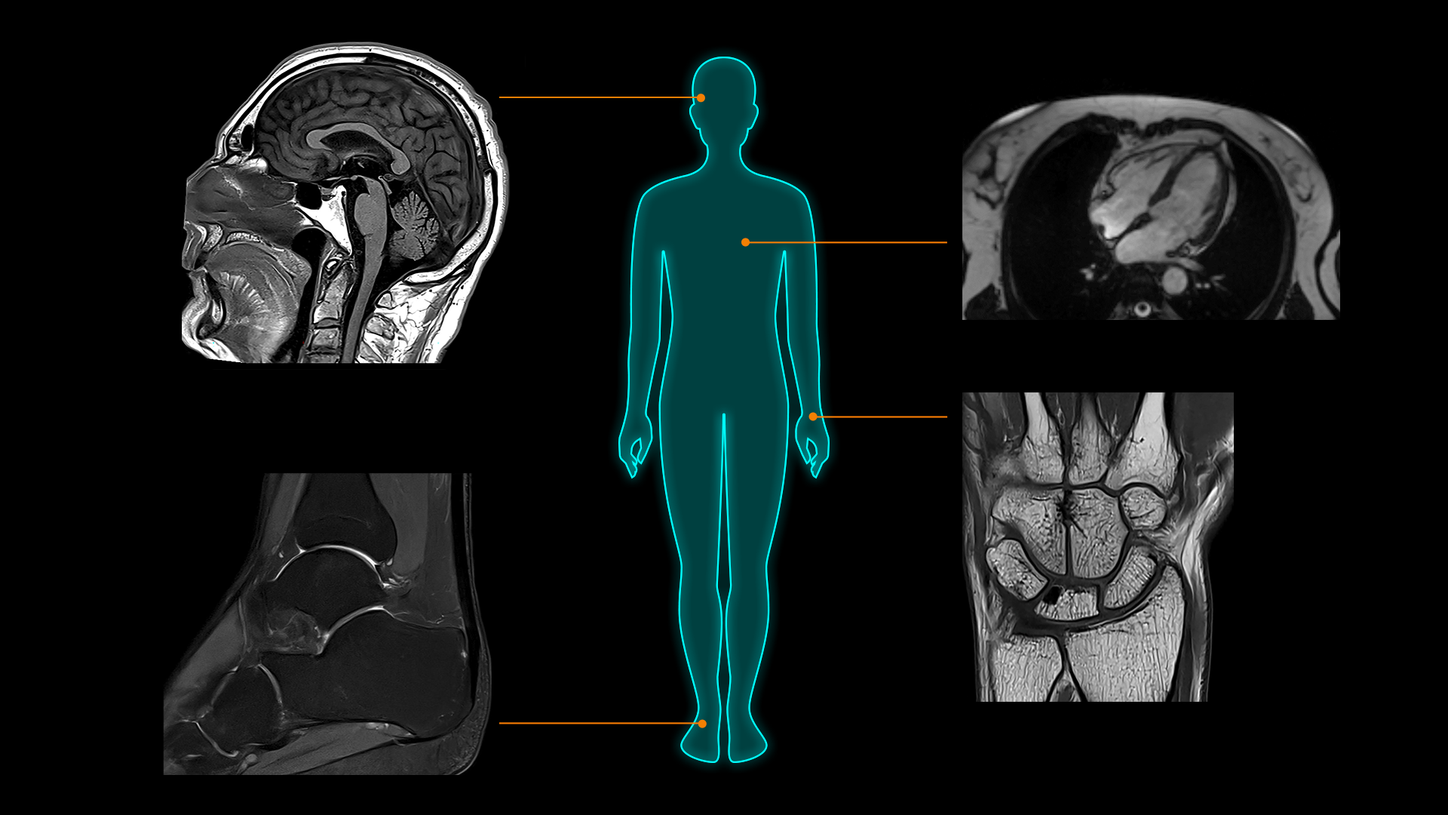

MAGNETOM Flow. Platform is designed to deliver highest-quality imaging for every clinical discipline. From routine imaging and screening to advanced imaging, from head to toe and from cardiac to oncology cases, it is planned to adapt to a wide range of imaging needs. Regardless of the type of institution, throughput demand, or clinical specialty, MAGNETOM Flow. Platform will empower you to achieve clinical excellence.